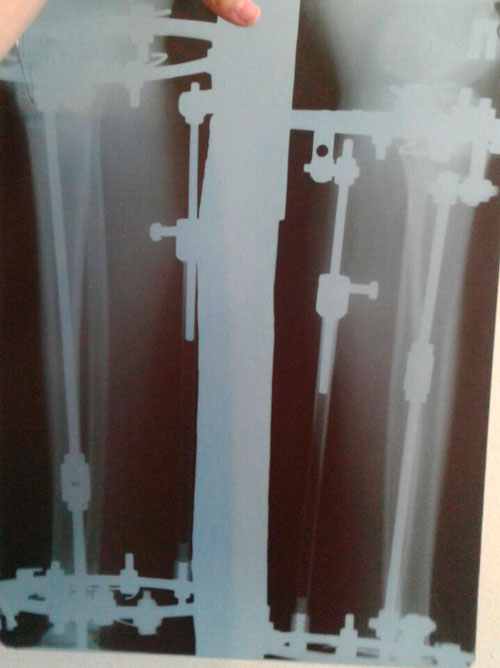

рентген перед фиксацией аппаратов.

SAM_0492.JPG

SAM_0493.JPG

Рентген в 60 дней

Пора на снятие аппаратов!

IMG-20160527-WA0011.jpg

IMG-20160527-WA0010.jpg